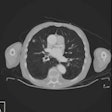

Ultrasound elevates diagnosis of pulmonary embolism

CT practice proves vital in mass casualty incidents

Mobile stroke units, spectral CT take spots on ECRI watch list